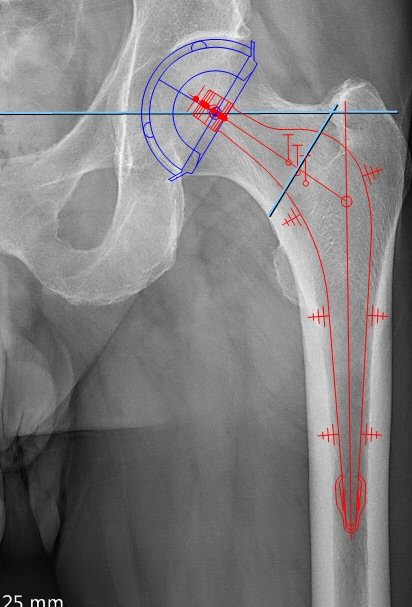

Kupp och stam positionerade på referenslinjen vilket ger oförändrad benlängd

Kupp, stam, offsetmätning, osteotomilinje och mätning av stammens placering i djupled